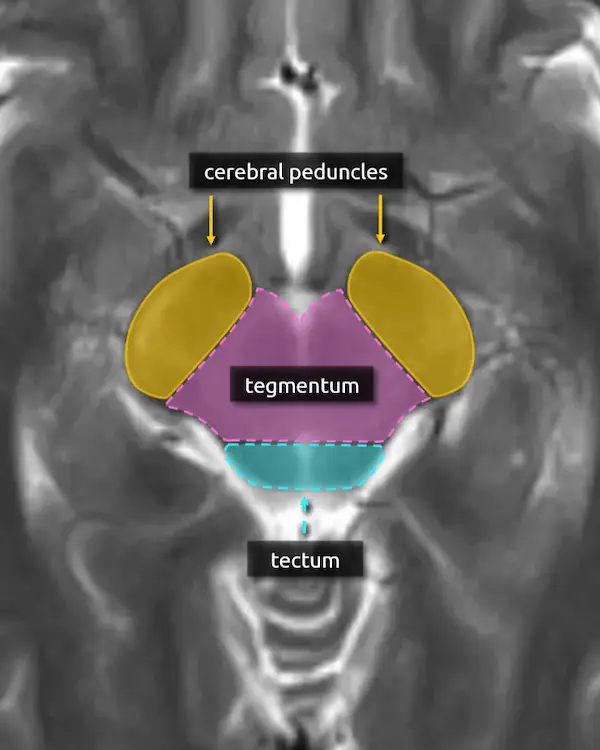

The brainstem can also be divided up into the basis, tegmentum, and tectum.

The basis, or base, simply refers to the anterior portion of the brainstem, which contains predominantly white matter tracts. In the midbrain, this corresponds to the cerebral peduncle. In the pons, it corresponds to the basis pontis; the bulbous part containing the transverse pontine fibers, corticospinal tract, etc. In the medulla, it corresponds to the pyramids.

The tegmentum is the central part of the brainstem. It contains the majority of the brainstem nuclei, including of the cranial nerves and structures of the reticular formation. Like the basis, there are white matter tracts that run through the tegmentum, some of which have been covered here. For example, recall the central tegmental tract, introduced in level 4 in reference to the triangle of Guillain-Mollaret, whose name should make more sense now, and the medial lemniscus.

The tectum is only located in the midbrain and is yet another way to refer to the superior and inferior colliculi (recall "quadrigeminal plate").